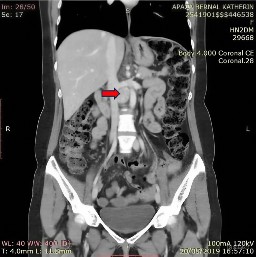

Posteriormente, se realizó un estudio de tomografía abdominal contrastada con resultado de una masa sólida de bordes definidos localizados en el espacio retroperitoneal de la región intercava, inmediatamente anterior al disco intervertebral L2-L3, que medía 26 x 23,9 x 28,8 mm, con realce intenso a la aplicación de sustancia de contraste sugestiva de paraganglioma retroperitoneal (Figura 1 y Figura 2).

Figura 1 Estudio de tomografía computarizada del abdomen: masa sólida de bordes definidos ubicada en el espacio retroperitoneal de la región intercava

Figura 2 Estudio de tomografía computarizada del abdomen: realce intenso a la aplicación de sustancia de contraste sugestiva de paraganglioma retroperitoneal